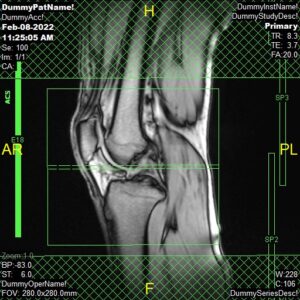

PD Sagittal, PD FatSat Sagittal and T2 Sagittal

Parameters

Sagittal Oblique

Sample Image